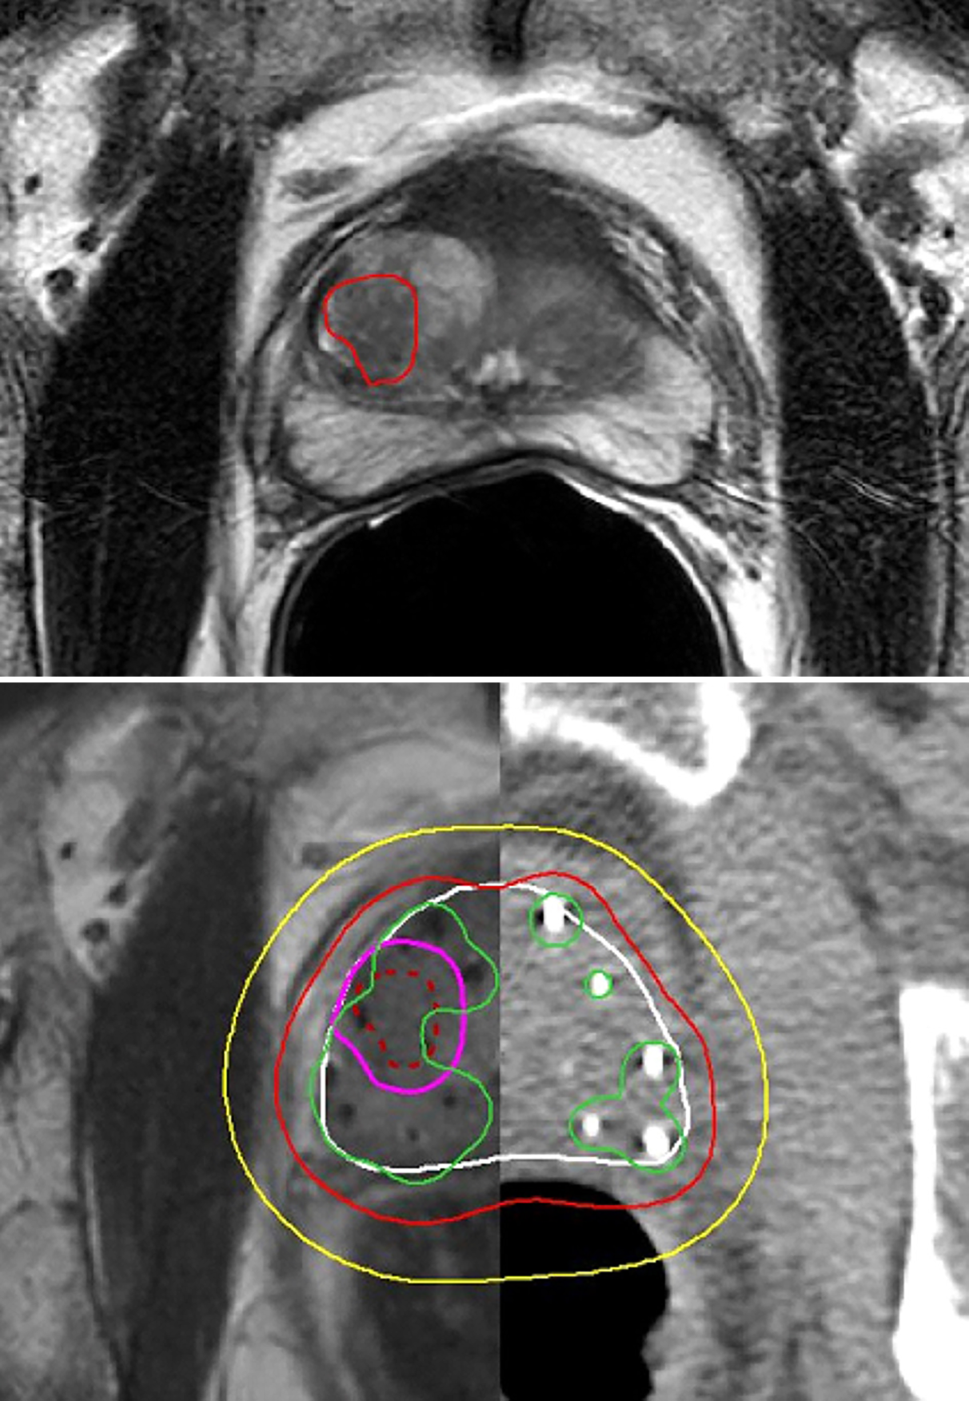

In fig. 9 zijn de verschillende beelden en de dosisverdeling van een van de 26 onderzochte gevallen weergegeven, waarbij de ingetekende diagnostische T2-gewogen MRI werd geregistreerd met de postimplantatie-MRI en -CT. Er waren elf cases met 1 GTV, tien met 2 GTV’s en vijf met drie GTV’s.

Figuur 9

Boven: diagnostisch T2-gewogen MRI-beeld met ingetekende GTV. Onder: postimplantatie-T2-gewogen MRI-beeld (links) geregistreerd met het CT-beeld voor herkenning van de zaadjes (rechts). De diagnostische MRI is geregistreerd met de postimplantatie MRI, zodat de ingetekende GTV ook zichtbaar is op dit beeld. Rond het GTV is een marge van 3 mm aangebracht tot aan het prostaatkapsel. Isodosen: geel 72,5 Gy, rood 145 Gy (voorgeschreven dosis), groen 290 Gy

De gemiddelde ± 1 sd van D90 van de prostaat was 169 ± 21 Gy (spreiding 116–216 Gy), van de ingetekende GTV’s 247 ± 53 Gy (spreiding 153–389 Gy) en van de GTV’s met 3 mm marge tot aan het kapsel 228 ± 43 Gy (spreiding 158–337 Gy). De D90 van zowel het GTV als de GTV met marge was significant hoger dan de D90 van de gehele prostaat (T-test p < 0,001).